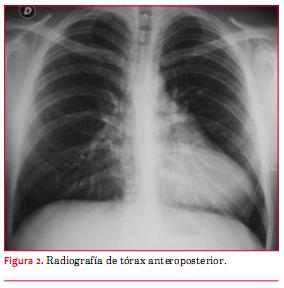

La radiografía de tórax (figura 2) mostró una silueta cardíaca desplazada a izquierda, con el borde derecho de la columna vertebral “desnudo”. El arco aórtico es normal, la arteria pulmonar impresiona aumentada y la silueta ventricular tiene una forma elongada muy peculiar. Se observa interposición de tejido pulmonar entre la silueta cardíaca y el diafragma.

En la radiografía de tórax la masa cardíaca desplazada a izquierda deja desnudo el borde derecho de la columna vertebral. La arteria pulmonar y la orejuela izquierda son prominentes pues desbordan los límites habituales del mediastino. La imagen del ventrículo izquierdo tiene una forma peculiar elongada y aplanada que ha sido llamada “signo de Snoopy” (por analogía con el perfil del personaje de historieta). Es frecuente ver interposición de tejido pulmonar entre el corazón y el diafragma, así como una “lengüeta” de tejido pulmonar que se introduce entre la aorta y la arteria pulmonar debido a la ausencia del receso pericárdico preaórtico(7).